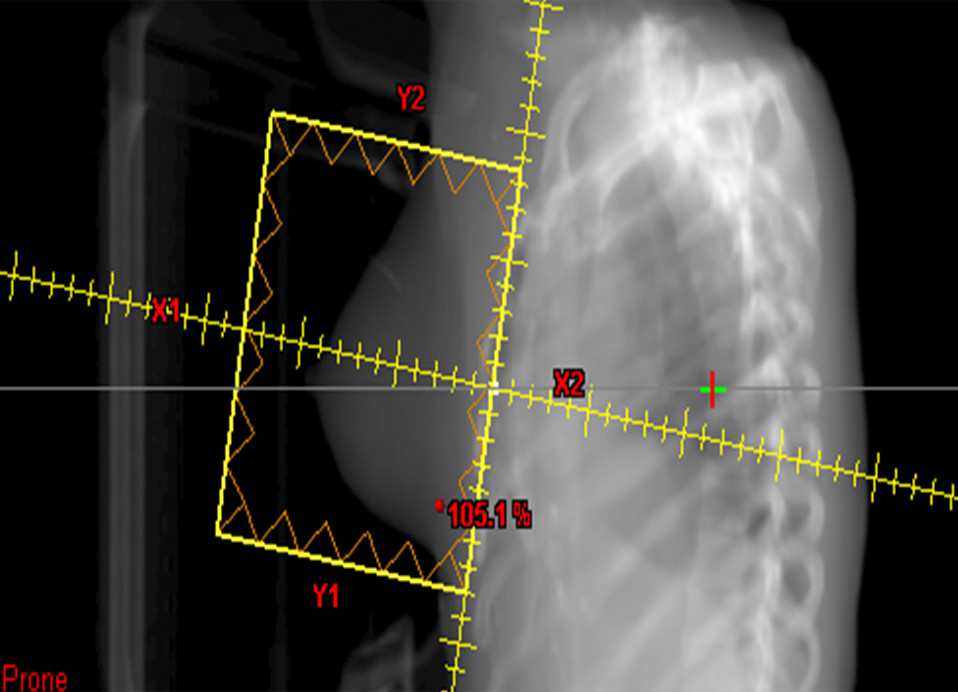

As a part of the conditioning regimen for bone marrow or stem cell transplant, radiation oncologists at the Cancer Center of Hawaii may recommend Total Body Irradiation (TBI) to enhance a patient’s immune suppression while destroying tumor cells. Essentially, TBI involves the use of radiotherapy to stop the growth of cancer cells throughout the whole body. This type of radiation can be highly effective for treatment of cancerous cells in bone marrow, such as leukemia, lymphoma or myeloma cells.